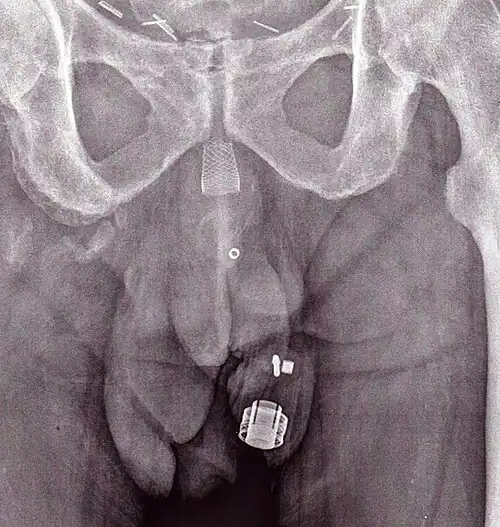

An X-ray image of implanted ZSI 375. The device is deactivated – the spring is compressed below the top of the cylinder. Patient is incontinent. -

An X-ray image of implanted ZSI 375. The device is activated – the spring is decompressed at the top of the cylinder. Patient is continent. -